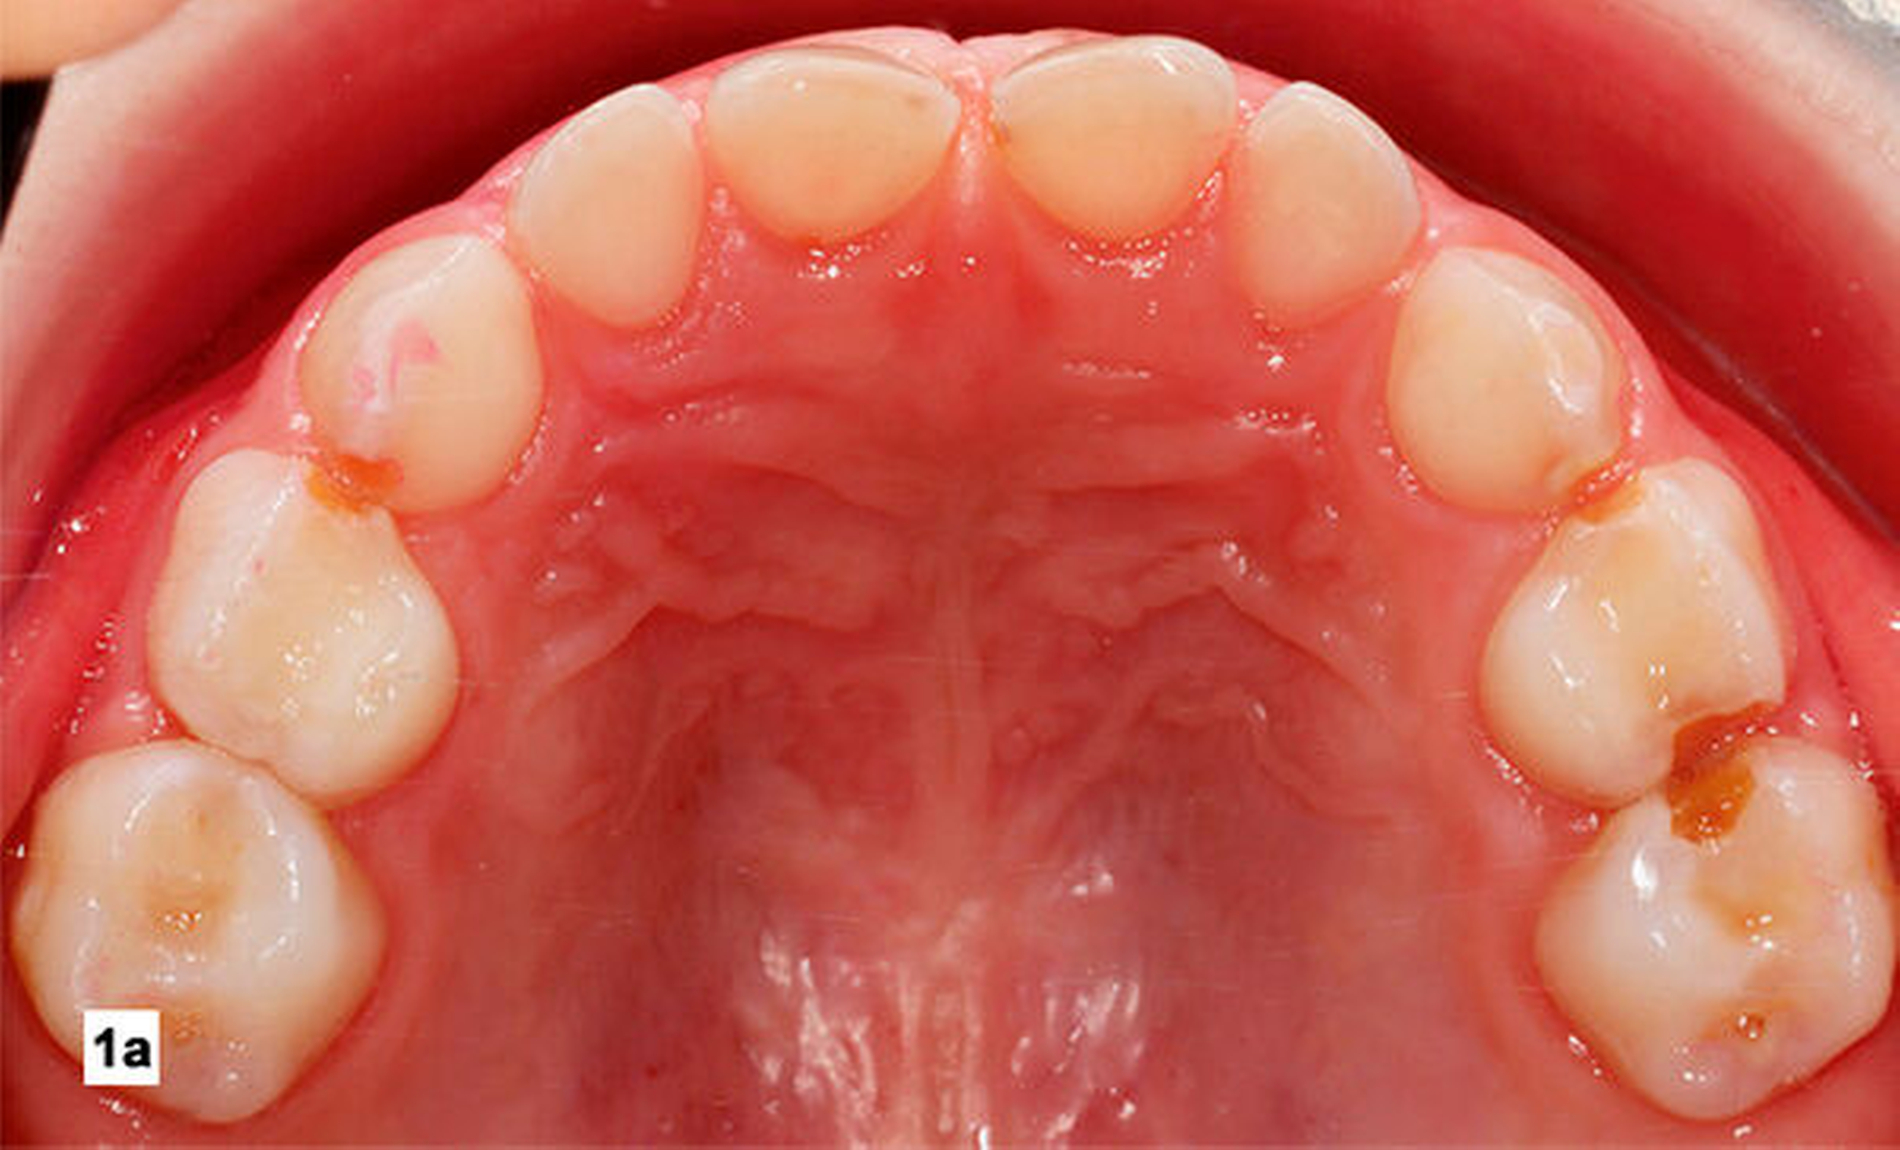

Generell existiert eine konsistente Evidenz, welche die Effektivität von SDF bei der Inaktivierung von koronaler Karies im Milchgebiss und bei der Arretierung und Prävention von Wurzelkaries bei Senioren belegt [Seifo et al., 2019; Chibinski et al., 2017). In Deutschland enthält das einzige verfügbare Produkt Silber-Fluorid-Ammoniak und Kalium-Jodid (Riva-Star®, SDI Dental Limited). Dieses Produkt wird allerdings in Europa im Unterschied zu Asien und Australien bis jetzt hauptsächlich als Desensibilisierungsmittel bei überempfindlichen Zähnen angewandt. Für die Kariestherapie ist die Nutzung von Silberprodukten hierzulande ein „Off-Label-Use“, aber trotzdem sicher und effektiv. Die Behandlung eines Patienten mittels SDF ist in den Abbildungen 1a und 1b dargestellt.